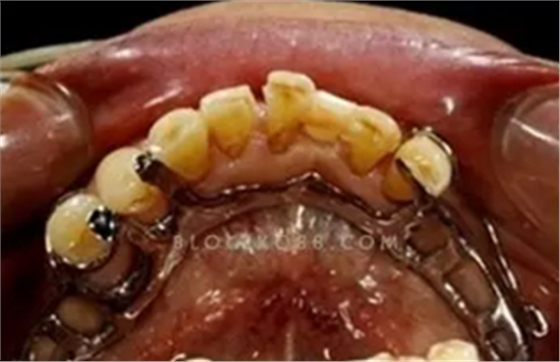

(八)RII

(思考靈感來自鬼才李望松,拜謝)

(圖24)

(圖25,棒子的)

是專門為近中游離端缺失時遠(yuǎn)中磨牙尤其是孤立的上頜磨牙設(shè)計的。臨床經(jīng)常遇見只剩最后二三個磨牙的近中游離端缺失情況,這時如何用卡環(huán),三臂卡?圈卡?倒置三臂卡?RPI?組合卡?這個問題在我腦里縈繞糾纏了很久,一個偶然的機會看到李望松的博客(圖24),雖說原圖不是為游離端設(shè)計的,但是卡環(huán)設(shè)計別具匠心,眼前一亮啊,趕緊查了查國外文獻(xiàn),我暈,居然已經(jīng)有名有姓的常規(guī)使用好多年了,就連韓國棒子也早已正兒八經(jīng)把它編進(jìn)了教科書。組成包括近中合支托、近中鄰面板、頰側(cè)I桿、舌側(cè)I桿,均為鑄造。頰側(cè)I桿位于頰面遠(yuǎn)中,進(jìn)入倒凹0.25mm起固位作用;舌側(cè)I桿要粗壯堅硬一些,位于遠(yuǎn)舌軸角處,為對抗臂。頰側(cè)亦可用其他設(shè)計,如用圓環(huán)形卡臂的RAI:

(圖26)

舌側(cè)I桿也可變換如下:

(圖27,引自李望松)